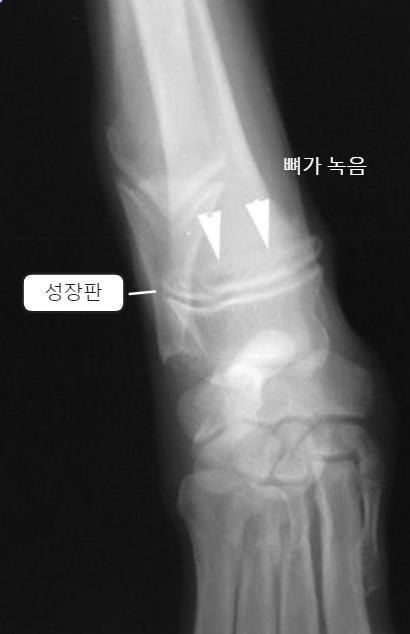

| - ์๋์ชฝ๋ง ์์์ผ๋ก ์ปค์ง๋ฉด์ flaring ์์์ ๋ณด์. | Early sign - Metaphyseal soft tissue swelling | ๋น์ ์์ ์ธ periosteal reaction์ด ์ฌํ๊ฒ ๋ํ๋จ, ์ฑ์ฅํ๋ ์์ ๋ฐ์ |